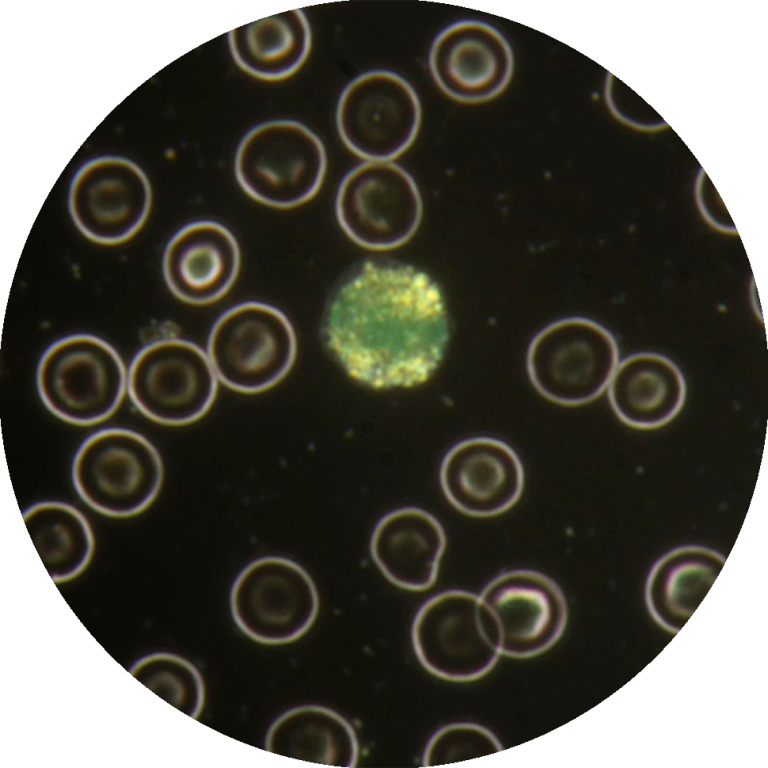

Aprofundar a Identificação Microscópica: Fornecer conhecimentos detalhados sobre a morfologia e ciclos de vida dos principais parasitas encontrados em amostras sanguíneas (ex: Babesia, Anaplasma, Dirofilaria) e fecais (ex: ovos e oocistos de nematóides, cestóides, trematóides e protozoários), utilizando as modalidades de campo claro e campo escuro.

Utilizar a Microscopia de Campo Escuro: Ensinar a aplicação da microscopia de campo escuro para a visualização de parasitas no seu estado vivo, permitindo a observação de motilidade e características que podem perder-se em preparações fixas.

A microscopia continua a ser a técnica laboratorial de eleição para o diagnóstico de infeções parasitárias, sendo as técnicas de coloração, usadas na preparação da amostra, o fator decisivo para um diagnóstico correto e eficaz.